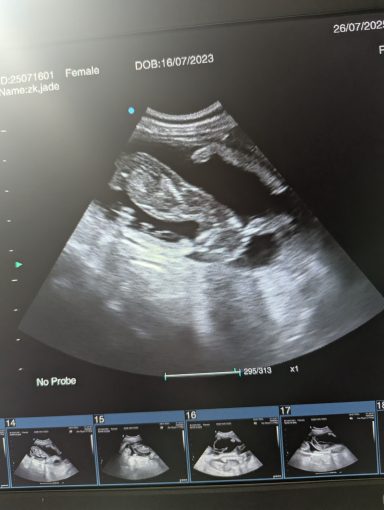

Pregnancy ultrasound scanning - Our pregnancy ultrasound service provides safe, non-invasive confirmation of pregnancy in both dogs and cats. Using advanced scanning technology and gentle handling techniques, we deliver clear, reliable results while prioritizing your pet’s comfort and wellbeing.Whether you visit our calm, home-based clinic or book a mobile appointment, we tailor each session to suit your pet’s needs—supporting responsible breeding with compassion, precision, and care.

Ultrasound pregnancy scanning is a safe, non-invasive way to confirm pregnancy in dogs and cats, offering breeders and pet owners peace of mind and vital information to support responsible care. It allows us to detect gestational sacs, assess foetal development, and estimate litter size—all while ensuring the wellbeing of the animal.

Pregnancy can sometimes be detected as early as Day 18 post-mating, but scanning at this stage is not routinely recommended. Embryos are still developing and may not be clearly visible, and there is a natural risk of embryo resorption, which can lead to misleading or inconclusive results.

For the most accurate and reliable scan, we advise booking between Day 25 and Day 32, when pregnancy is more easily confirmed and foetal structures are clearer. If an early scan is performed and no pregnancy is detected, we offer a FREE complimentary re-scan after 7 days at the clinic to ensure clarity and support informed decision-making.

Our approach balances early insight with ethical care—always prioritizing the comfort of the animal and the accuracy of the results.